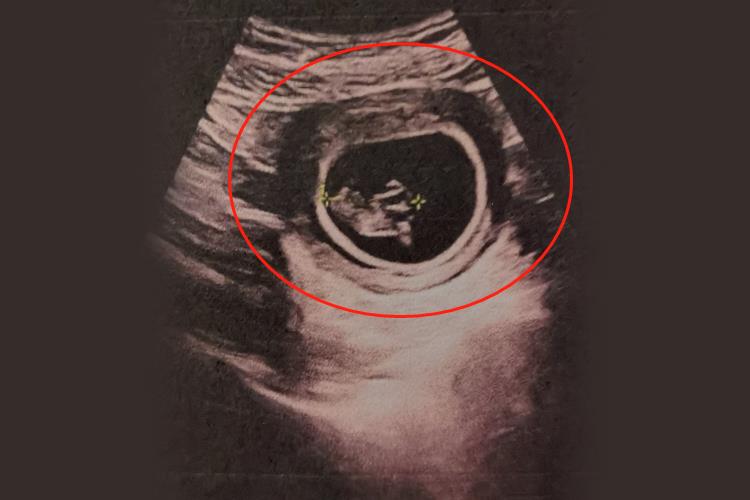

临床上并没有具体的孕9周子宫的大小,孕9周胎儿头臀长约30mm,此时胎儿的头、四肢、躯干可清晰显示。

临床上并没有明确孕9周子宫有多大,此时子宫尚未明显增大,与平时大小类似,平均长约7cm,只是子宫壁变软,宫颈逐渐增厚。此时为妊娠早期,子宫略呈球形且不对称,受精卵着床部位的子宫壁明显突出,胎儿基本成形,可辨认肱骨、股骨。